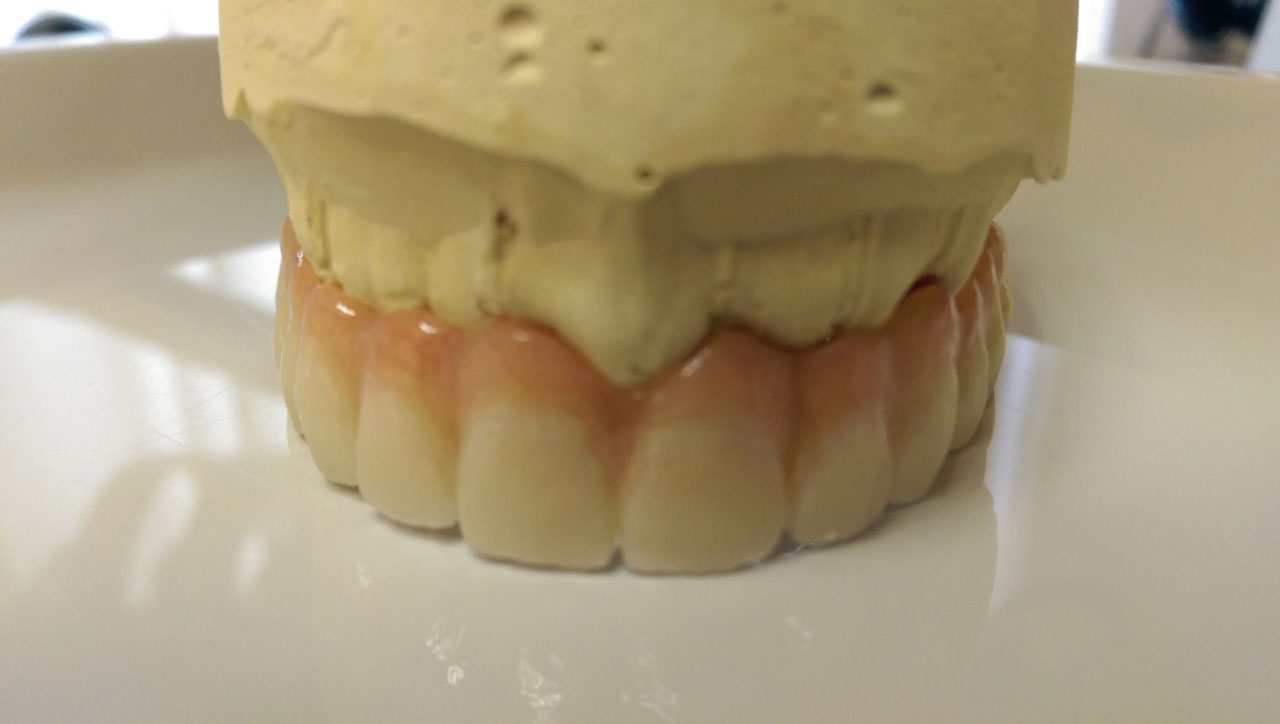

Sikerét mindenekelőtt a gyorsaságának köszönheti, hiszen a mai rohanó világban kinek van ideje, kedve fogatlanul otthon ülni heteket, hónapokat a fogpótlásra várva? Az Ihde implantációs eljárás során a páciens azonnal, de legkésőbb 72 óra múlva egy rögzített (tehát nem mozgó, nem kivehető) pótlással hagyja el a rendelőt. Ez az egyedülállóan gyors eljárás annak köszönhető, hogy azonnal tudunk implantálni szinte bárhova, akár foghúzás után is, továbbá a művelet nem jár nagy feltárásokkal, nincs szükség csontbeültetésre, így a gyógyulás folyamata is nagyon gyors és a beültetés technikájának köszönhetően maximum 72 óra múlva a korona is feltehető. Tehát ennyi idő alatt foga lesz a betegnek és az implantátum azonnal terhelhetővé is válik.

A gyorsaság, a biztonság mellett, a lehető legkevesebb elszenvedett fájdalom jellemzi még az Ihde fogpótló rendszert. Egyrészt, kevesebb időt tölt az érintett személy a fogorvosnál, másrészt, minimális a behatoló fizikai beavatkozás és kisebb az összműtéti terhelés, ami a fájdalmakat is minimalizálja.